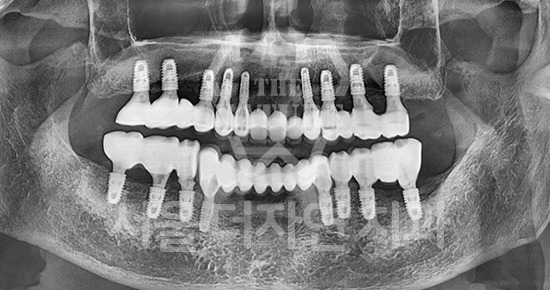

#전체 임플란트

-

BEFORE: 2022.12.15

AFTER: 2023.02.23